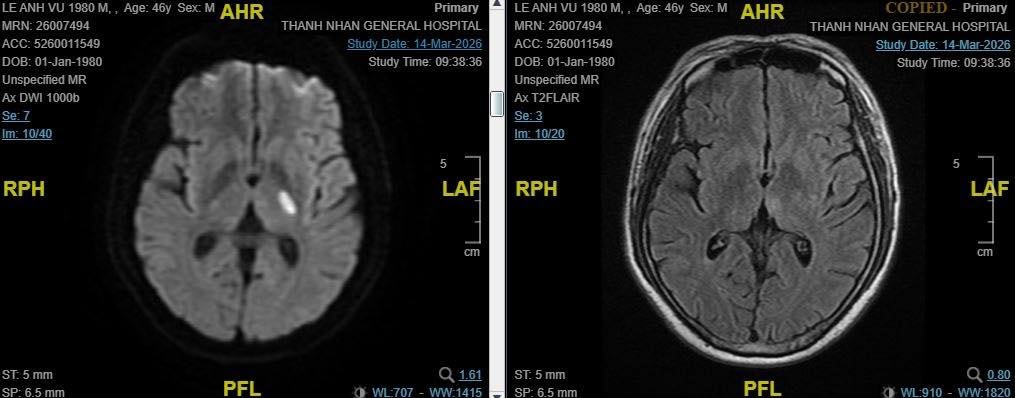

Ngay khi nhập viện, bệnh nhân được thăm khám, chụp chiếu và đánh giá nhanh tình trạng. Các bác sĩ xác định đây là trường hợp nhồi máu não và đủ điều kiện sử dụng thuốc tiêu sợi huyết - phương pháp có thể làm tan cục máu đông nếu can thiệp trong “khung giờ vàng”.

Kết quả chụp MRI ghi nhận tổn thương não do đột quỵ Ảnh: BVCC